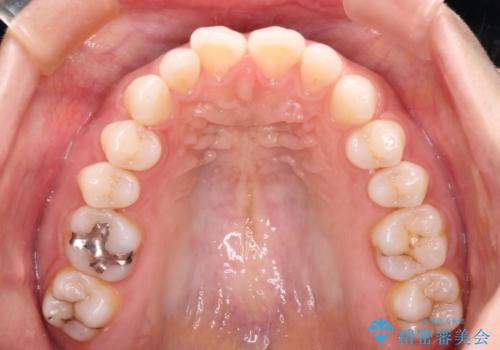

唇が閉じにくい ワイヤー装置での抜歯矯正

- 唇が閉じにくく、上の前歯が下唇に当たって気になるとのことで来院された患者様です。

レントゲン写真での分析結果からは、抜歯矯正をするかどうか悩む境界線上でしたが、主訴が口元の突出感であったため、上下左右の第一小臼歯4本を抜歯して矯正治療を行うこととしました。

上下ともに前歯が少し舌側に傾斜したような仕上がりとなりましたが、口が閉じやすくなったとのことで、患者様には大変満足していただけました。